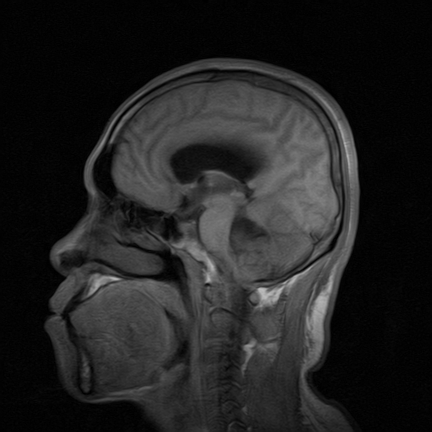

标题: MRI2064:少见病例。男性52,视力下降多年。 [打印本页]

标题: MRI2064:少见病例。男性52,视力下降多年。

四脑室区见混杂信号占位影,脑室系统扩张明显,临近结构显著受压称位,患者52岁,多考虑室管膜瘤可能性大

考虑第四脑室室管膜瘤并阻塞性脑积水。

考虑第四脑室室管膜瘤并梗阻性脑积水;部分性空蝶鞍;左侧上颌窦粘膜下囊肿。

考虑第四脑室室管膜瘤【血供丰富血管母细胞瘤可能】并梗阻性脑积水;部分性空蝶鞍;左侧上颌窦粘膜下囊肿。

比较典型的脉络丛乳头状瘤并脑积水,鉴别小脑蚓部血管母细胞瘤。